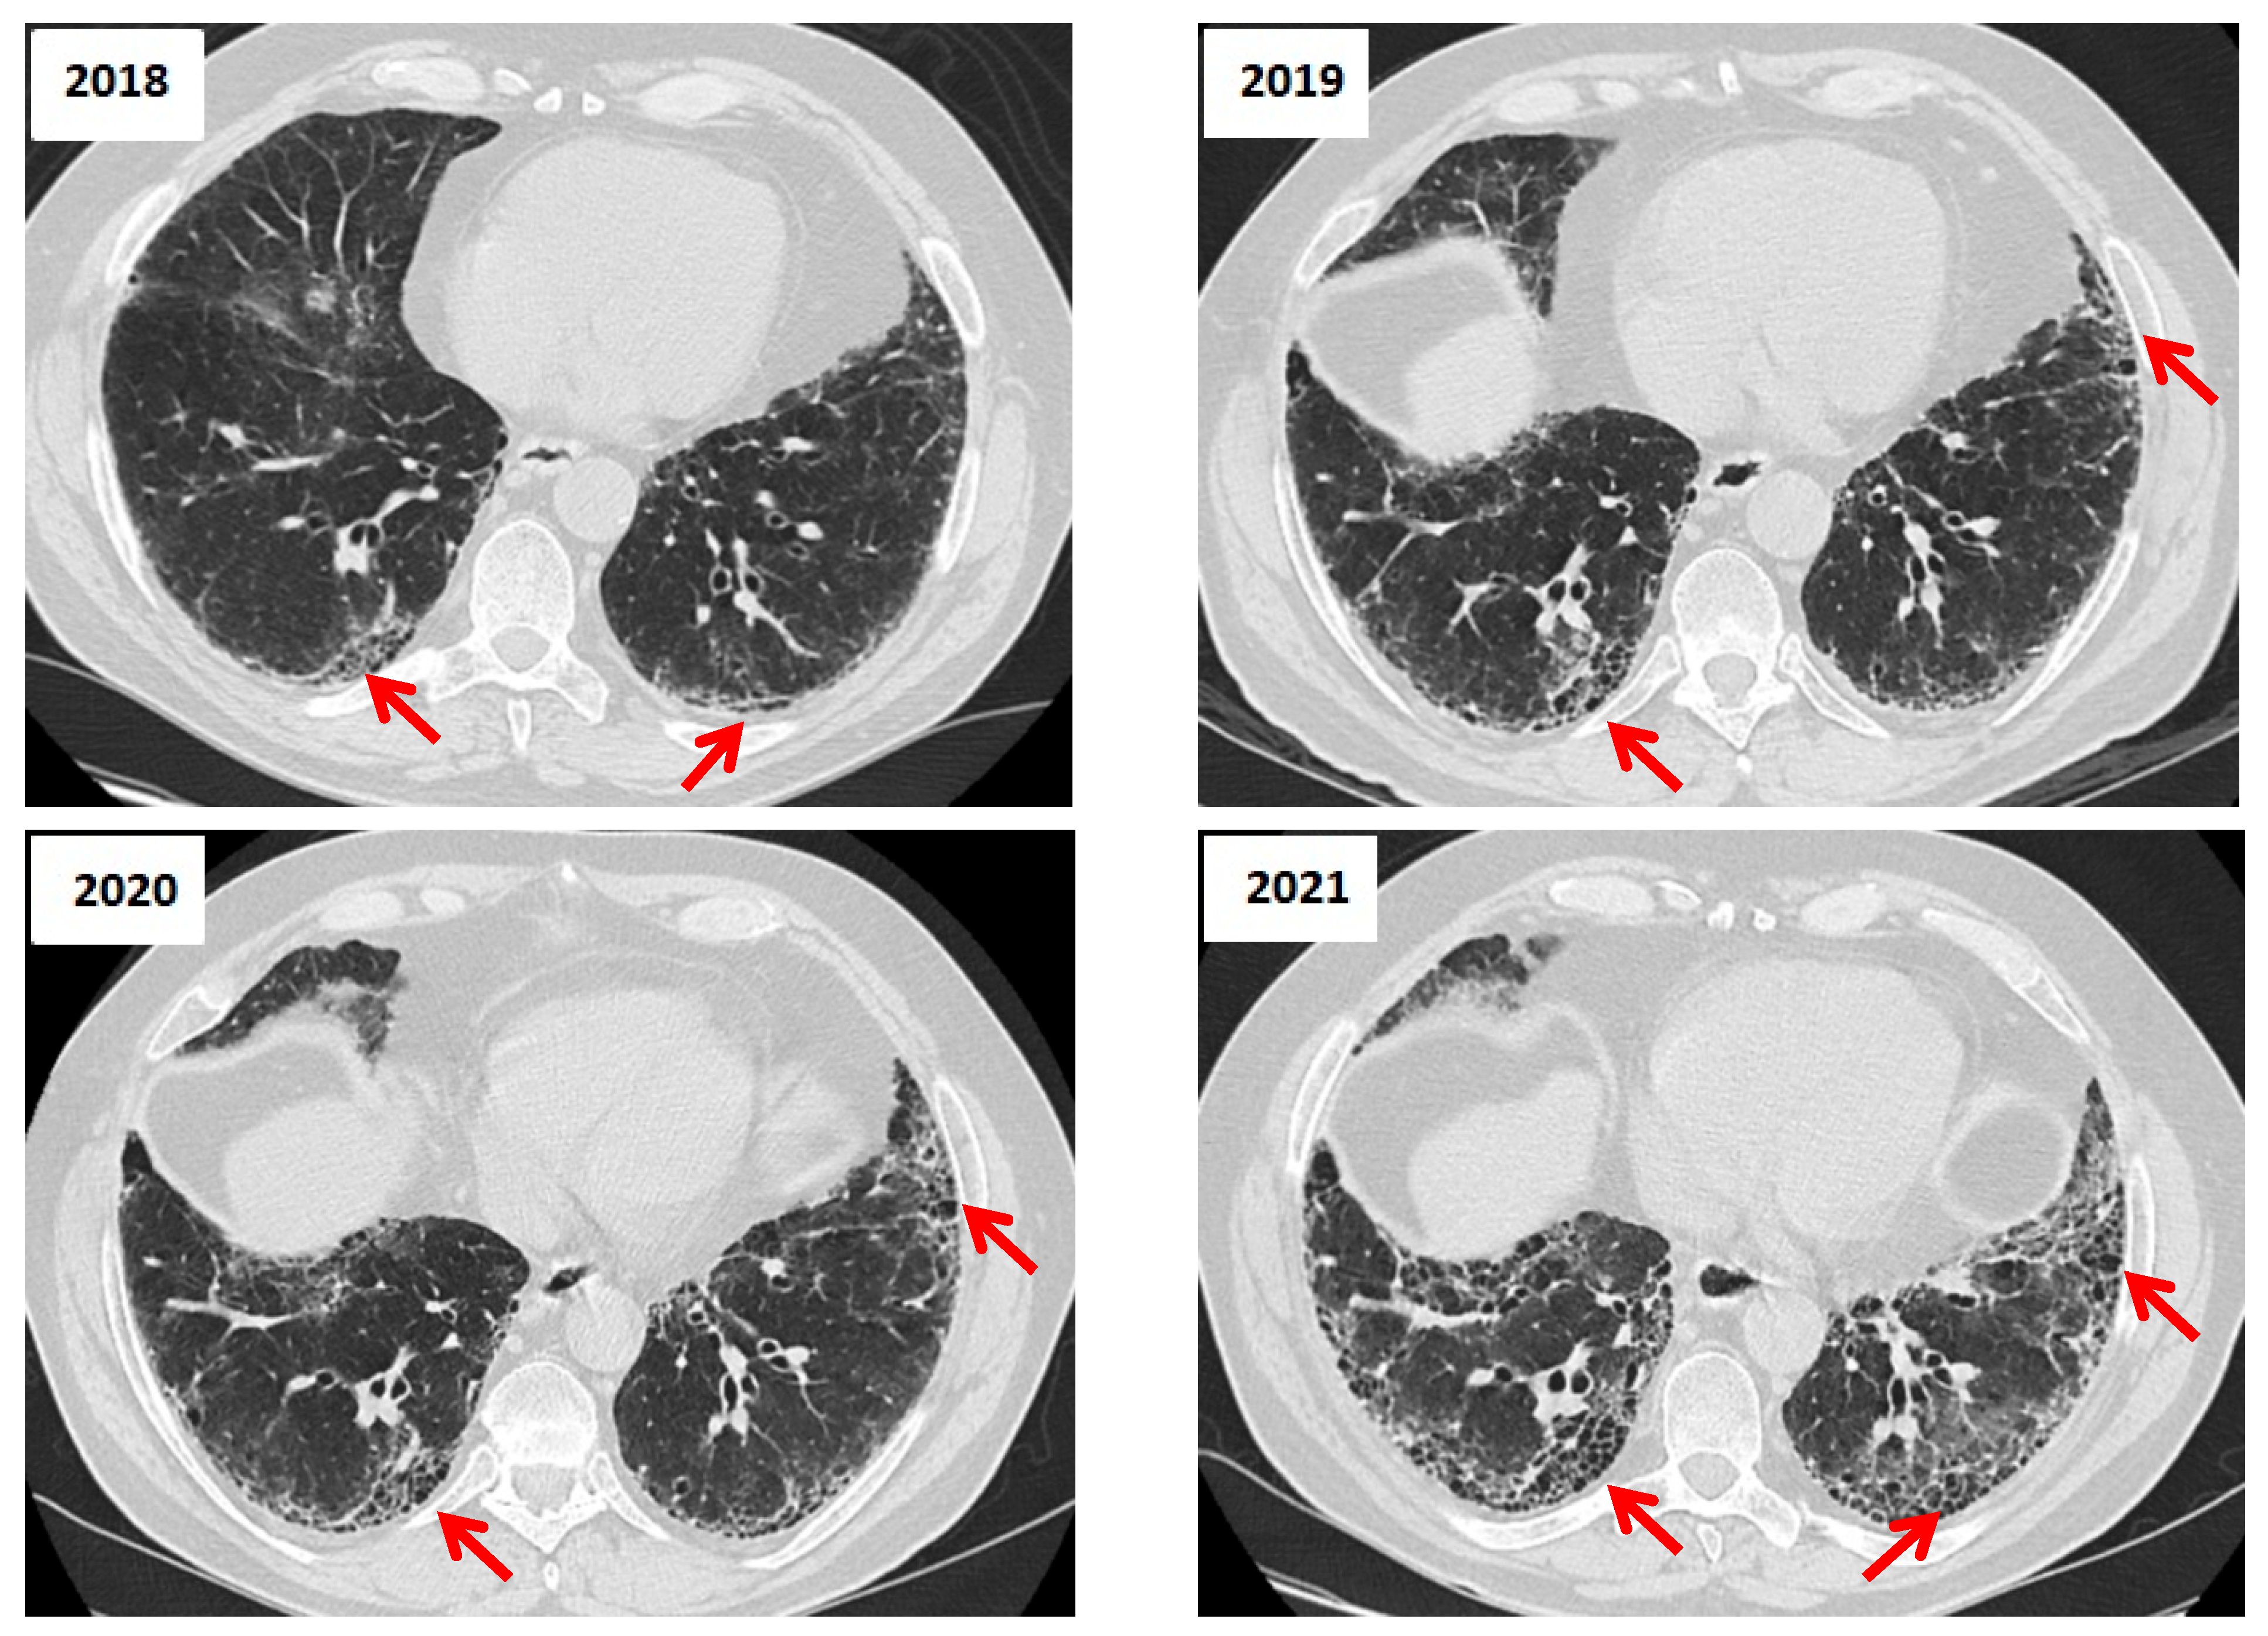

3.5. Role of HRCT in Longitudinal Assessment of CTD-ILD

| HRCT Patterns | - UIP is the most common pattern (~40–60%)—strong negative prognostic marker - NSIP (~15–25%) - OP and mixed types less frequent. (<20%)  | [43] |

| Distinctive HRCT Signs | - Anterior upper lobe (AUL) sign  - Straight-edge (SE) sign - Exuberant honeycombing (EHC)  | [45] |